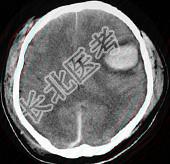

- 单项选择题女,52岁, 有高血压病史,半小时前突感头晕, 剧烈头痛,摔倒在自家楼下, CT检查如图所示,最可能的诊断是 ( )

E、脑出血